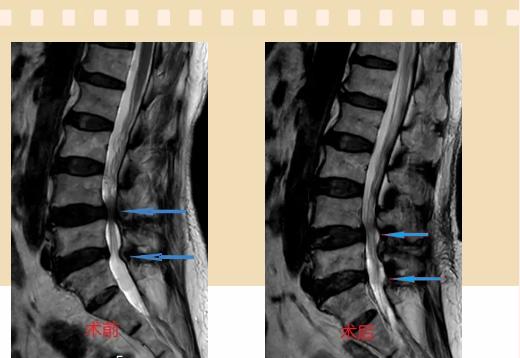

入院后李鵬副主任醫(yī)師為其進(jìn)行了詳細(xì)的查體,完善了術(shù)前的檢查,明確診斷為:腰椎管狹窄癥(L4/5、L5/S1),病人合并2型糖尿病,請內(nèi)分泌科會診,穩(wěn)定血糖后,麻醉科會診病人,排除手術(shù)禁忌,李鵬為病人制定了手術(shù)方案:單側(cè)入路雙側(cè)減壓(ULBD)。

手術(shù)采用三個(gè)微創(chuàng)小切口,兩個(gè)節(jié)段減壓手術(shù)時(shí)間2.5小時(shí),出血50ml。術(shù)后2天腰圍保護(hù)下床活動,術(shù)后5天順利出院。

傳統(tǒng)腰椎管狹窄癥的手術(shù)治療,往往需要切開減壓,同時(shí)需要內(nèi)固定融合術(shù),創(chuàng)傷很大,同時(shí)可能需要輸血,臥床時(shí)間較長,病人合并糖尿病,感染風(fēng)險(xiǎn)也高,而本次采用的UBE-ULBD手術(shù)切口更?。悠饋砑s3cm,如果是單節(jié)段狹窄只需要不到2cm切口)、創(chuàng)傷更小,術(shù)后恢復(fù)較快,可以更早地恢復(fù)正常活動。

此外,手術(shù)保留了病變節(jié)段的穩(wěn)定性,是一種微創(chuàng)的椎管減壓手術(shù),能通過切除部分椎板、關(guān)節(jié)突關(guān)節(jié)、黃韌帶來解除神經(jīng)根和硬膜囊的壓迫,不需要額外行腰椎內(nèi)固定術(shù),不需要螺釘及融合器的植入,病人術(shù)后腰椎的活動度不受影響。(盧   闖  劉   旭   袁錦鈺)